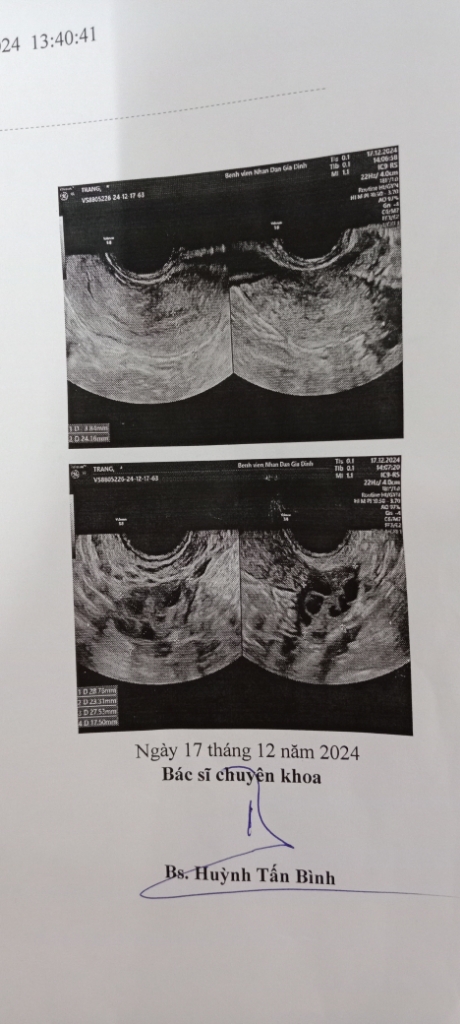

Em thấy triệu chứng giống bị PCOS nhưng sau khi siêu âm thì bác sĩ phụ khoa báo bình thường ( em vẫn hơi lo) dưới đây là ảnh, xin bác sĩ xem giúp em được không ạ